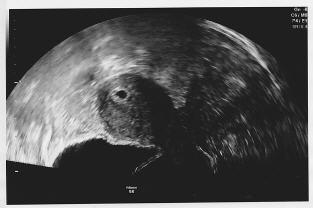

Hallo zusammen, ich war gestern bei 5+3 zum ersten Mal beim FA, da ich auf Nummer sicher gehen wollte, das der Wurm sich richtig eingenistet hat. Dabei kam das angehängte US Bild zustande. Man sieht die Fruchthöhle, sonst nichts. Der Arzt meinte, das wäre zu der Zeit völlig normal und in 2 Wochen habe ich einen Folgetermin. Jetzt hab ich aber gelesen, das man zu der Zeit schon mehr erkennen können sollte. Bin natürlich jetzt total verunsichert ob sich da noch was entwickelt oder ob ich das abschreiben kann. Es ist meine erste SS und ich bin jetzt natürlich wieder total verunsichert :( Wie war das bei euch zu dieser Zeit? LG Bea

Bild zu Frage an die Profis - Schwanger - wer noch? Rund um die Schwangerschaft

Mein erster US war auch bei 5+3.. und mehr konnte man auf meinem Bild auch nicht sehen! P.s: Die Fruchthöhle war 0,67 cm "groß"

Völlig normal. Bei mir war bei 5+6 die Fruchthöhle mit Dottersack zu sehen, zwei Wochen später ein Gummibärchen von 1,57cm mit schlagendem Herz, wieder zwei Wochen drauf (32 Tage nach dem ersten US) ein 3,7cm Zwergi mit Herzschlag und Wirbelsäule. Ich häng mal ein Vergleichsbild dran. Mach dir keine Sorgen. In zwei Wochen siehst du das kleine Herzchen pumpern.